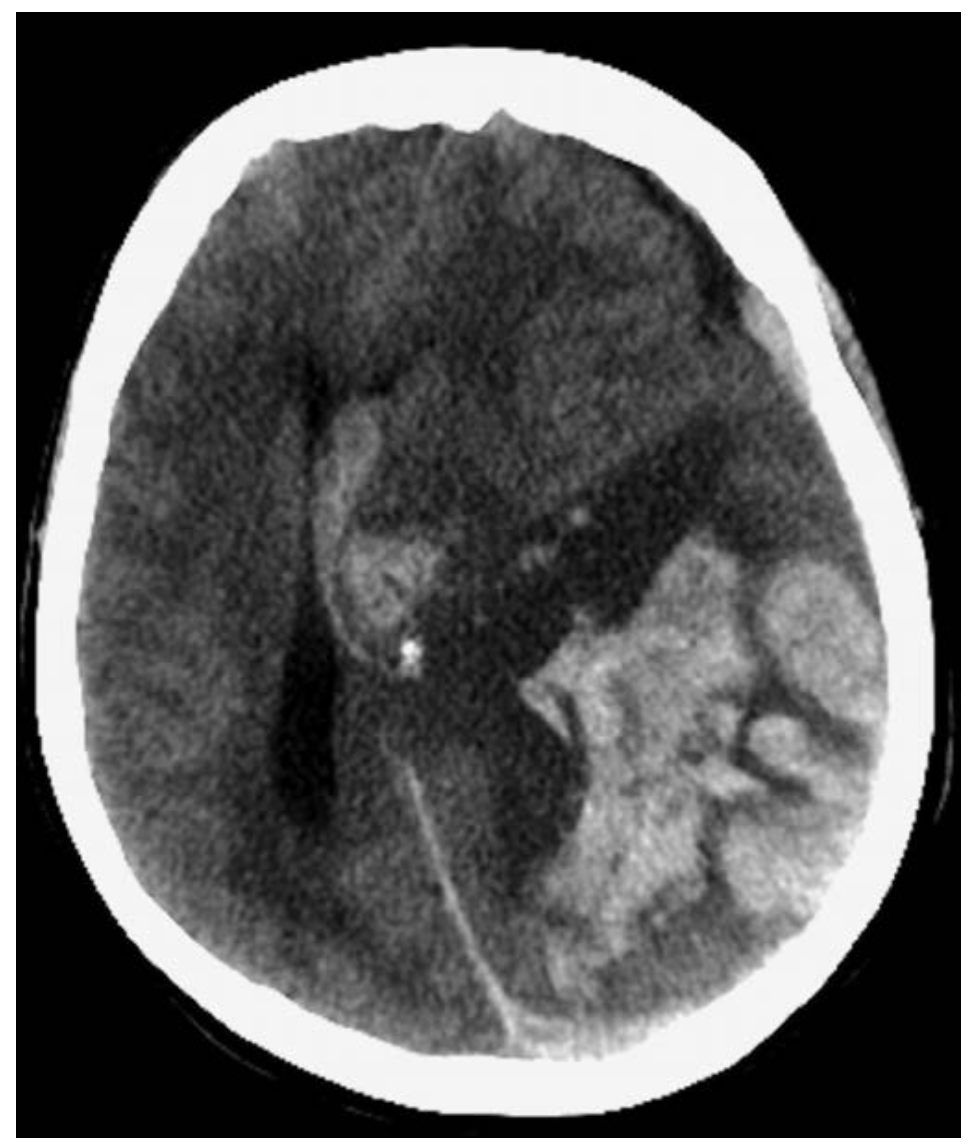

| Intracranial hemorrhage / subarachnoid hemorrhage |

두통, 신경학적 이상, 심할 경우 의식 저하 | brina CT, 경미한 subarachnoid hemorrhage의 경우 요추천자를 통해 진단 |